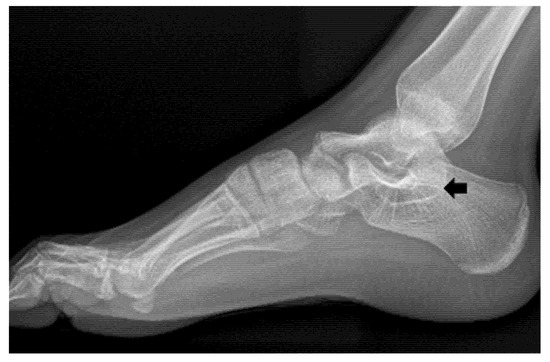

Bilateral Multiple Tarsal Coalitions (Talonavicular and Talocalcaneal Coalitions) with Recurrent Ankle Sprain in an Adolescent

2. Case Report